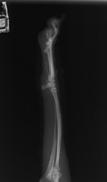

![]() 術後レントゲン検査(ラテラル像) |

![]() (AP像) |

![]() プレート抜去後(ラテラル像) |